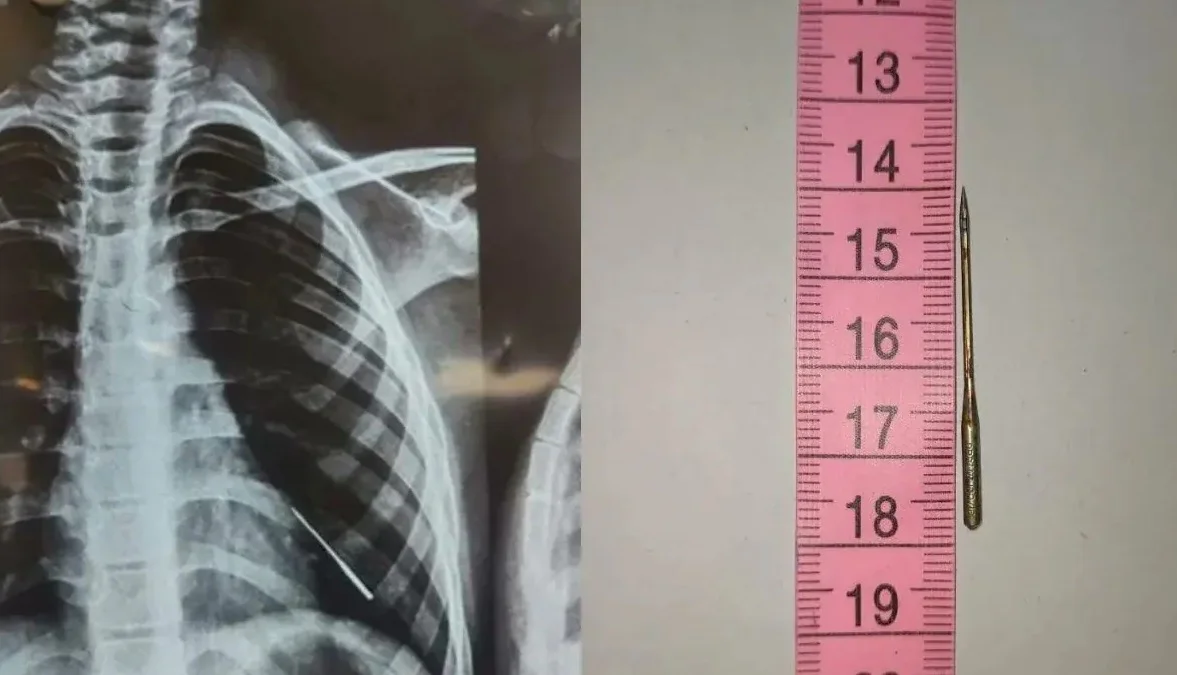

নজির গড়ল ভুবনেশ্বর এইমস, অস্ত্রোপচার ছাড়াই বালকের ফুসফুস থেকে বের করা হল সূঁচ